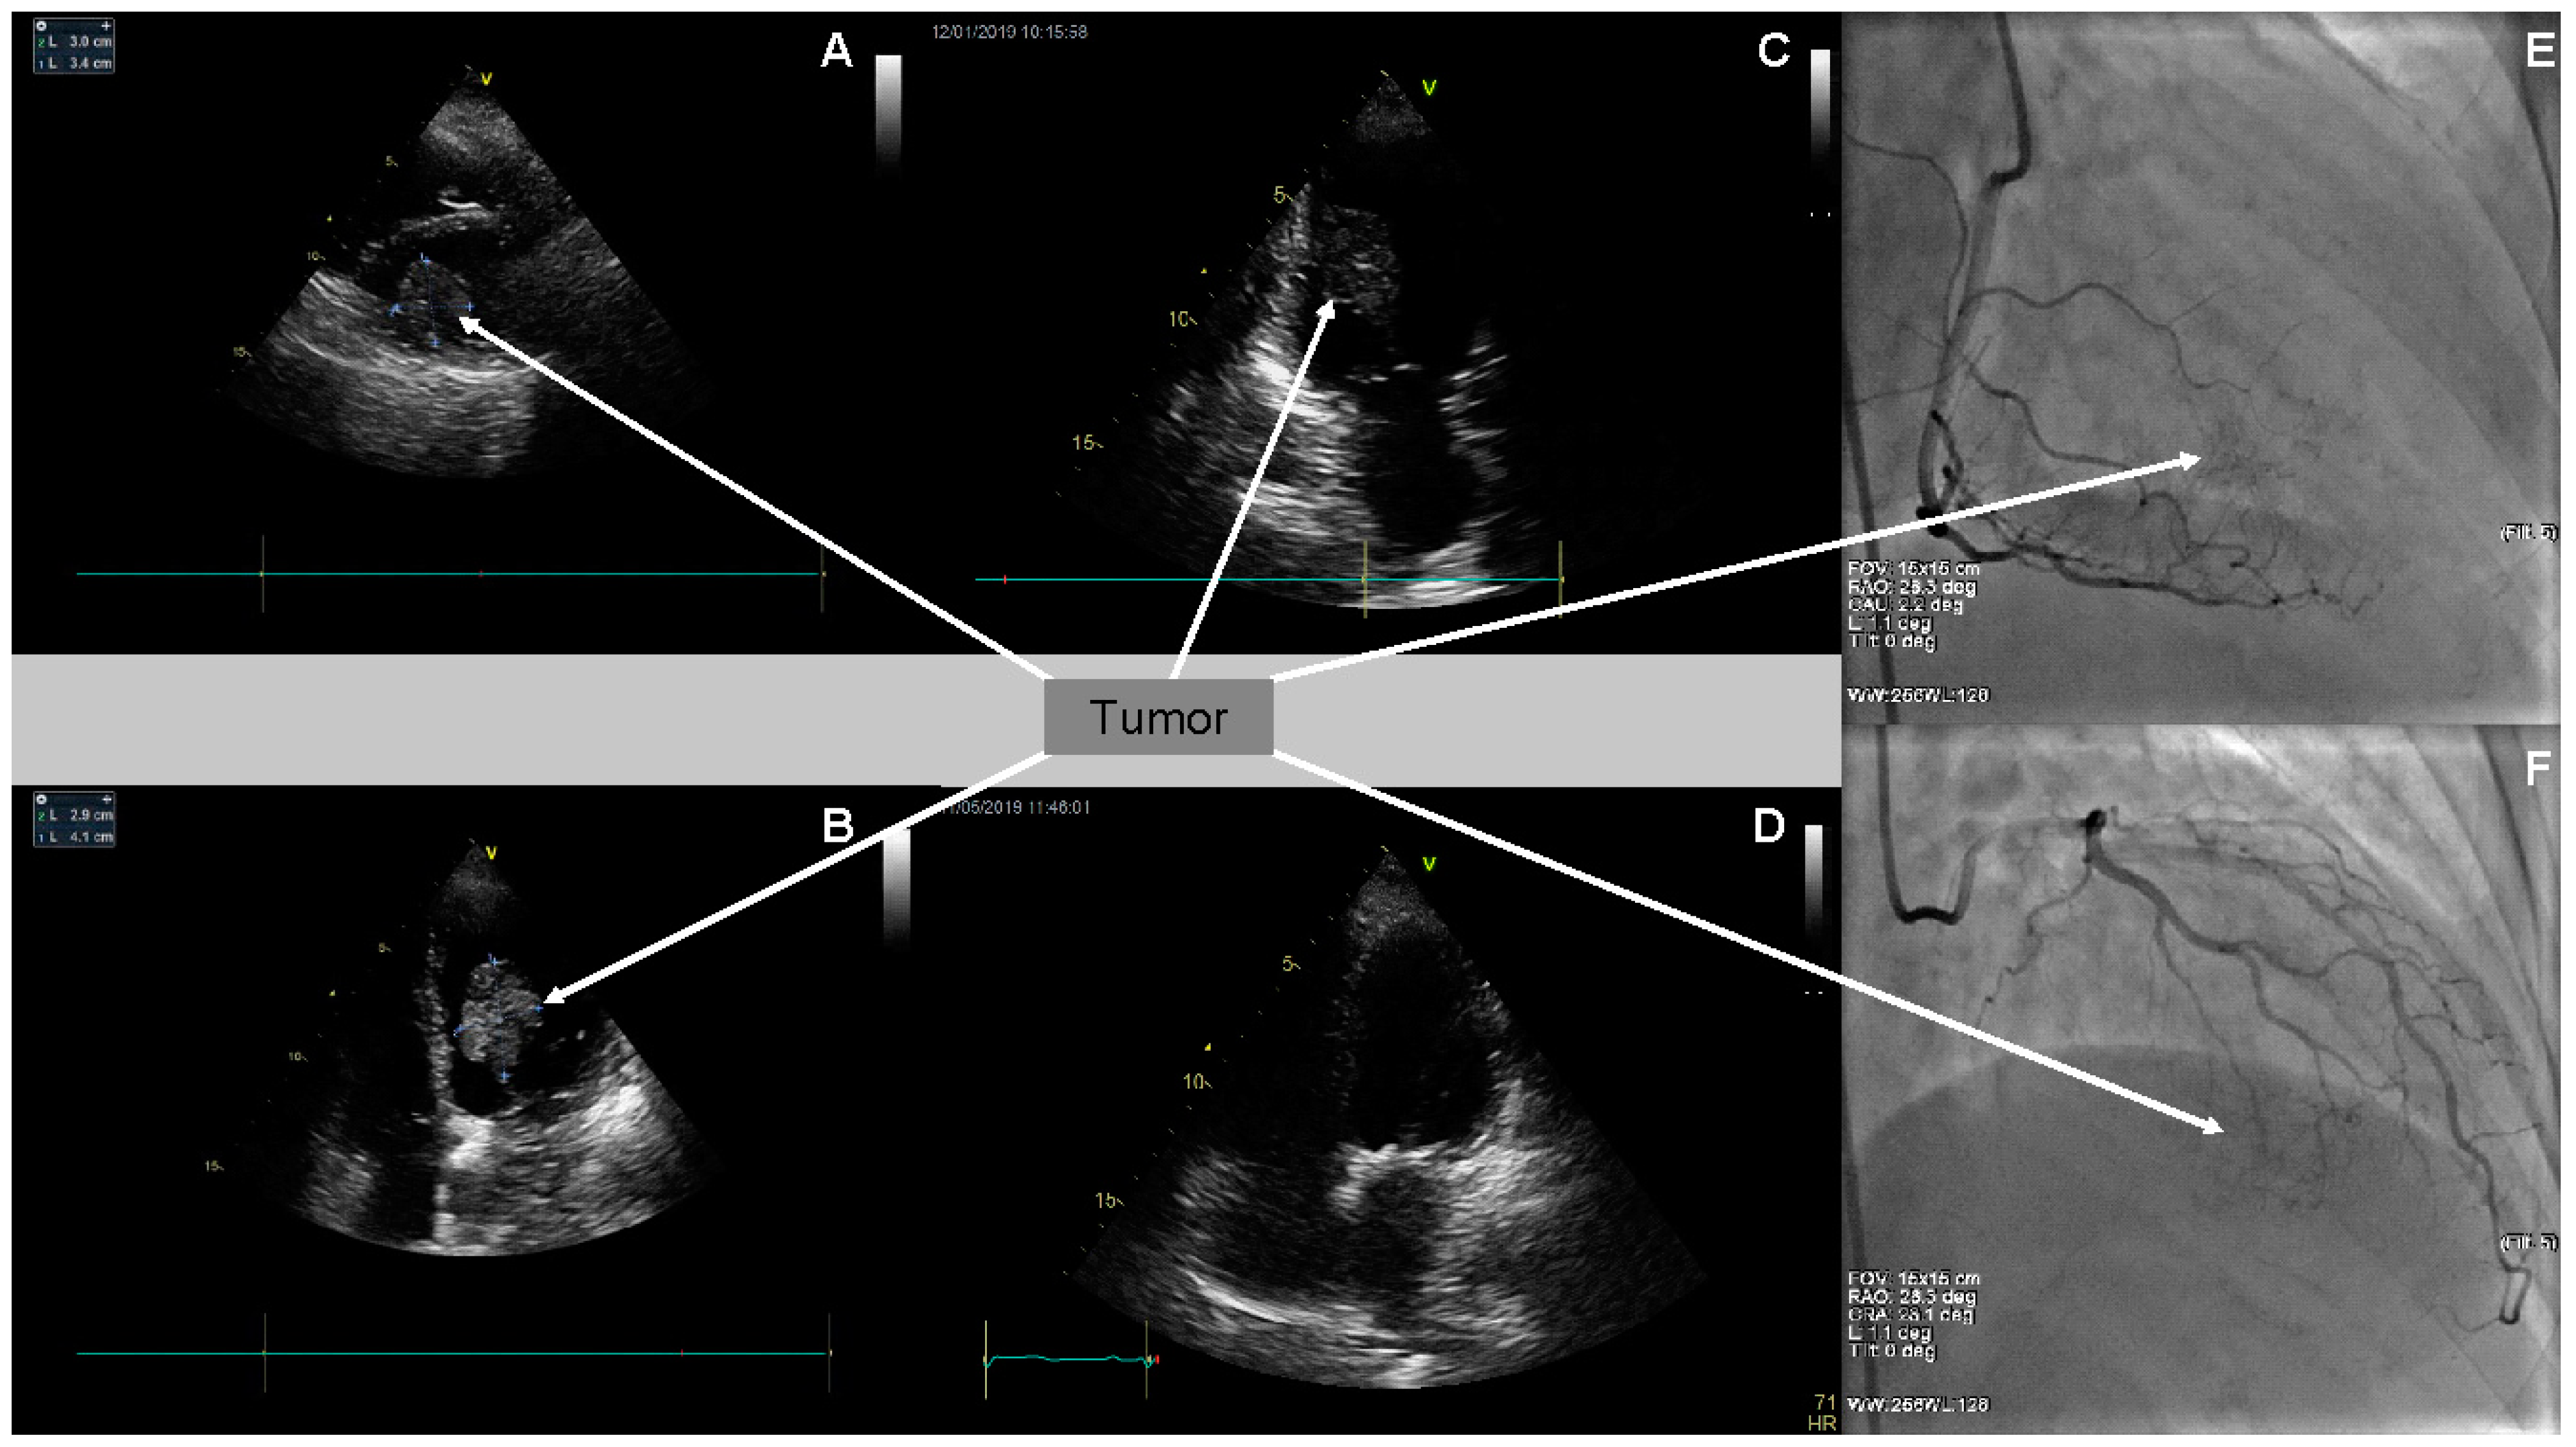

Two-dimensional transthoracic echocardiography (2D TTE) detected the presence of a large left ventricular mass, 3.0 × 3.4 cm in diameter, in the parasternal short axis presentation, and of 2.9 × 4.1 cm in four chamber (4-Ch) apical presentation (Figure 1A–C). Moreover, it confirmed moderate mitral regurgitation, small tricuspid regurgitation, and small aortic regurgitation. The dimensions of her heart cavities were normal, apart from enlarged left atrium dimension (LAd—4.5 cm). Global left ventricle contractility was preserved—LVEF assessed as 62%. Simultaneously, transesophageal echocardiography (TEE) assessed the tumor originating from and most probably infiltrating the inferior wall of the left ventricle, with singular fibrosis. The diagnosis suggested, on the basis of the TEE image, was left ventricular myxoma.

Due to retrosternal chest pain reported by the patient, coronary angiography (CA) was performed. The angiographic examination excluded significant changes in epicardial coronary arteries. Poor tumor vascularity at the late arterial phase of right coronary artery and circumflex branch of the left coronary artery selective angiography were visualized (Figure 1E,F).

On the basis of immunohistochemical examination result and due to the follow-up TTE confirming the tumor recurrence, the patient was urgently referred to the National Institute of Oncology in Warsaw. Considering the melanoma of an unknown origin with heart metastases as the most probable diagnosis, the intravenous treatment with Keytruda (pembrolizumab) was implemented. Pembrolizumab constitutes a potent, highly selective, fully humanized immunoglobulin (Ig) G4-kappa monoclonal antibody against PD-1 with potential immune checkpoint inhibitory and antineoplastic activities. Keytruda is used in patients with advanced melanoma and is now a standard of care in the first-line setting. Planned treatment consisted of intravenous pembrolizumab 10 mg/kg every three weeks. After the first pembrolizumab infusion, the patient was discharged and went home in a good clinical condition. Subsequent follow-up echocardiography performed on 1 May 2019 revealed no left ventricular tumor (Figure 1D). Moreover, it revealed an enlarged left atrium, moderate mitral stenosis, and small aortic and mitral regurgitation. Tricuspid regurgitation progressed to moderate. Modest interventricular septum hypokinesis was observed. Impaired left ventricular relaxation was confirmed.

Figure 1. Coronary angiography (CA) and transthoracic echocardiography (TTE). (A) CA (RAO 28.3°, CAU 2.2° presentation)—visible poor tumor vascularity at the late arterial phase of the right coronary artery selective angiography (arrow); (B) CA (RAO 26.3°, CRA 23.1° presentation)—visible poor tumor vascularity at the late arterial phase of the left coronary artery (circumflex branch) selective angiography (arrow). (C) Two-dimensional TTE (parasternal, short axis presentation)—tumor in the left ventricle cavity (arrow); (D) 2D TTE (apical 4-Ch presentation)—tumor in the left ventricle cavity (arrow); (E) 2D TTE (2-Ch presentation)—tumor in the left ventricle cavity (arrow); and (F) 2D TTE (4-Ch presentation)—tumor resolution after chemotherapy.